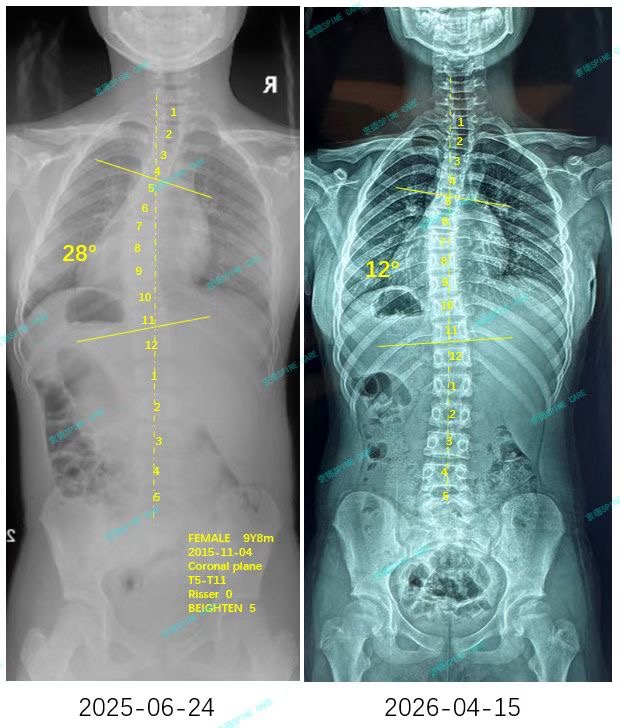

来自家长对衷德的评价(小瑜妈妈)

衷德脊柱,我们只关注侧弯保守治疗~

Zhongde Spine, bending no breaking ~